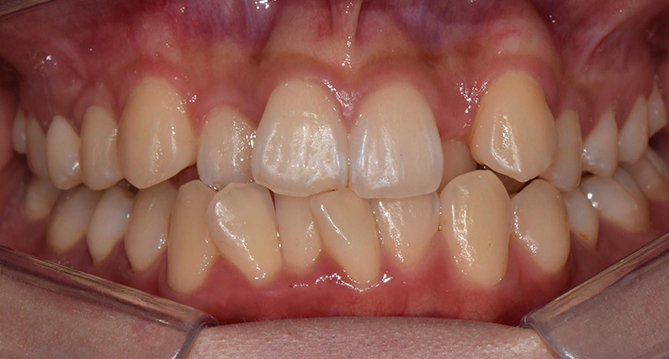

연세새빛치과 전체치아교정[클리피씨] 교정 전

연세새빛치과 전체치아교정[클리피씨] 교정 후